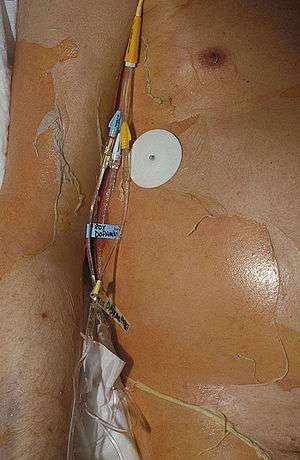

Toxic epidermal necrolysis (TEN), also known as Lyell's syndrome,[1] is a rare, life-threatening skin condition that is usually caused by a reaction to drugs.[2] The disease causes the top layer of skin (the epidermis) to detach from the lower layers of the skin (the dermis), all over the body, leaving the body susceptible to severe infection. The case fatality ratio ranges from 25 to 30%, and death usually occurs as a result of sepsis and subsequent multiorgan system failure. Treatment primarily involves discontinuing the use of causative agent(s), and supportive care in either the intensive care unit or burn unit of a hospital.[3][4]

Initial skin findings include red-purple, dusky, flat spots known as macules that start on the trunk and spread out from there. These skin lesions then transform into large blisters. The affected skin can then become necrotic or sag from the body and peel off in great swaths.[3]

Nearly all people with TEN have oral, eye and genital involvement as well. Painful crusts and erosions may develop on any mucosal surface.[11] The mouth becomes blistered and eroded, making eating difficult and sometimes necessitating feeding through a nasogastric tube through the nose or a gastric tube directly into the stomach. The eyes can become swollen, crusted, and ulcerated, leading to potential blindness. The most common problem with the eyes is severe conjunctivitis.[12]

The primary treatment of TEN is discontinuation of the causative factor(s), usually an offending drug, early referral and management in burn units or intensive care units, supportive management, and nutritional support.[3]